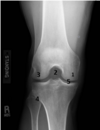

Which number is the intercondyloid fossa? A - 5 B - 4 C - 2 D - 3 E - 1

C - 2 The intercondyloid fossa (2) is the cavity formed between the condyles of the femur (C). This is best demonstrated utilizing tunnel views of the knee. The medial and lateral condyles of the femur are represented by (1) and (3) respectively (D and E). The proximal tibiofibular joint is labeled (4), and the tibial plateau is labeled (5) (A and B).